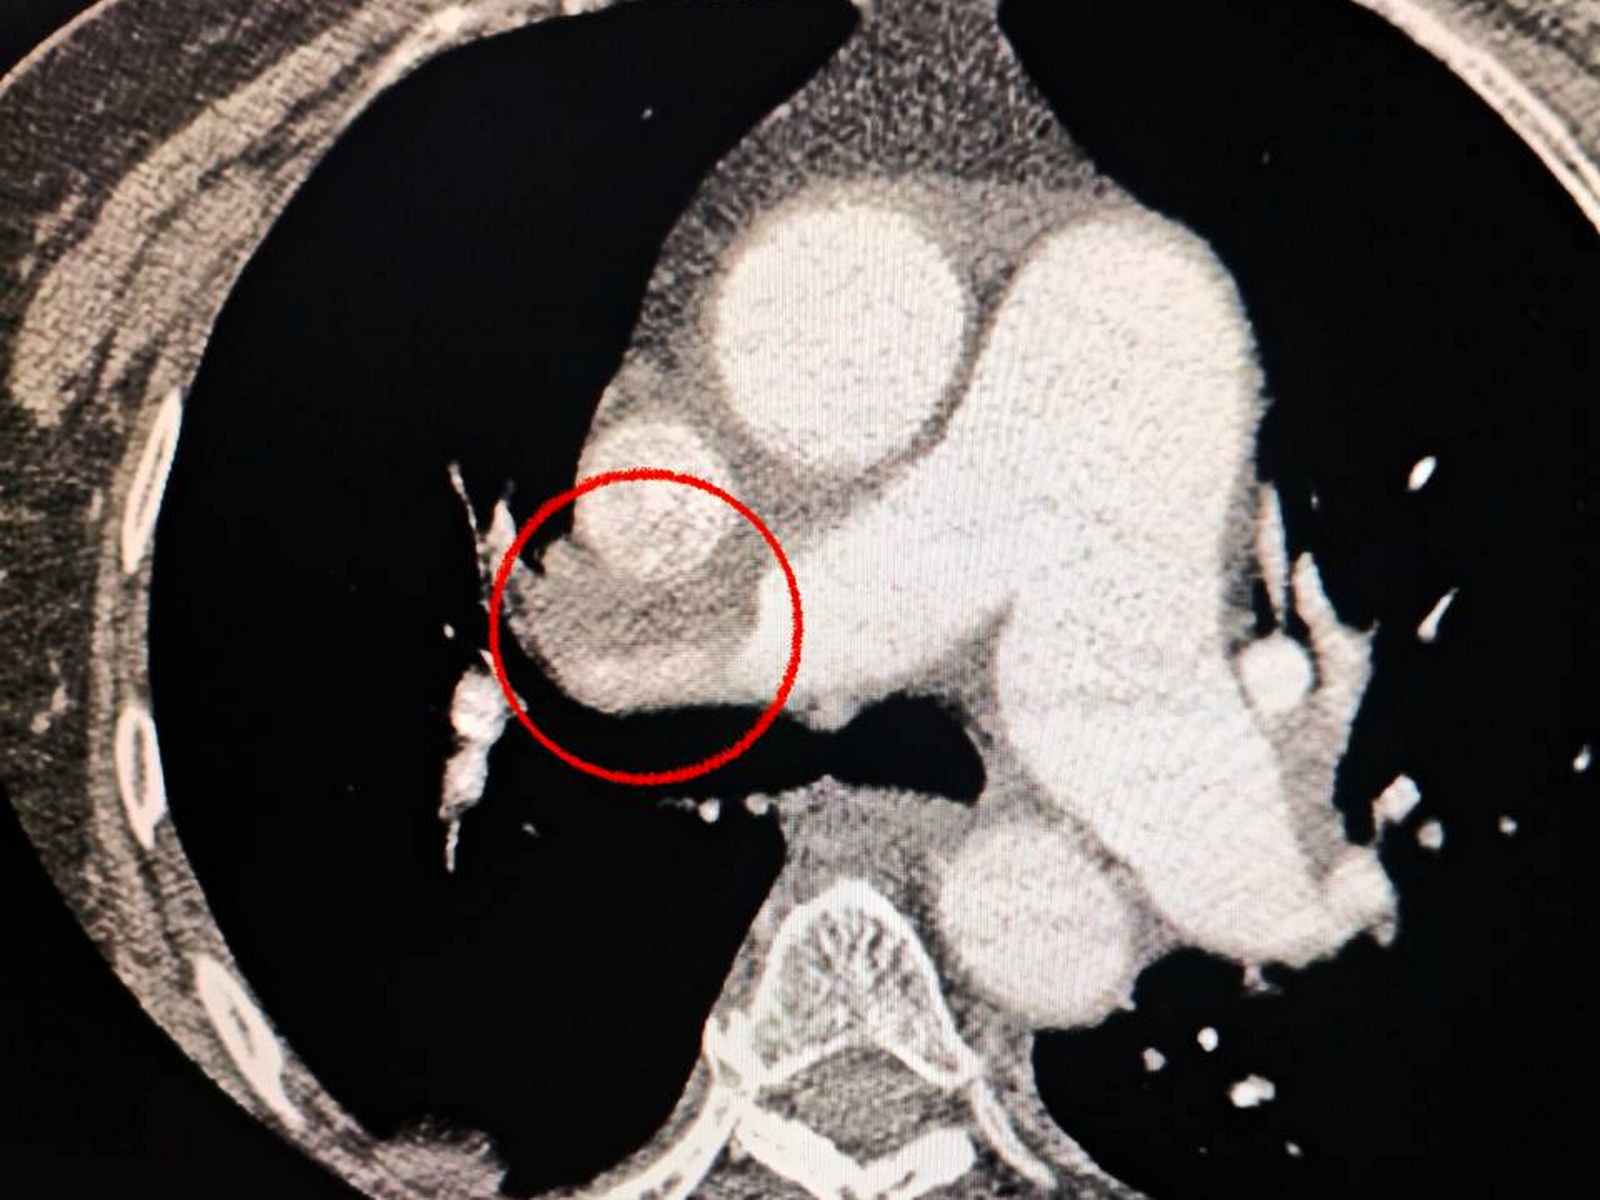

Одеситка потрапила до лікарні з важким гострим мозковим інсультом. Під час обстеження на комп’ютерному томографі лікарі виявили закриття середньої мозкової артерії. Також медики звернули увагу, що жінці важко дихати, тож додатково обстежили легені. Діагноз ускладнився ще й тромбоемболією легеневої артерії.

Мультидисциплінарна команда лікарів ухвалила життєво необхідне рішення – провести одночасну тромбектомію з мозкової та легеневої артерій.